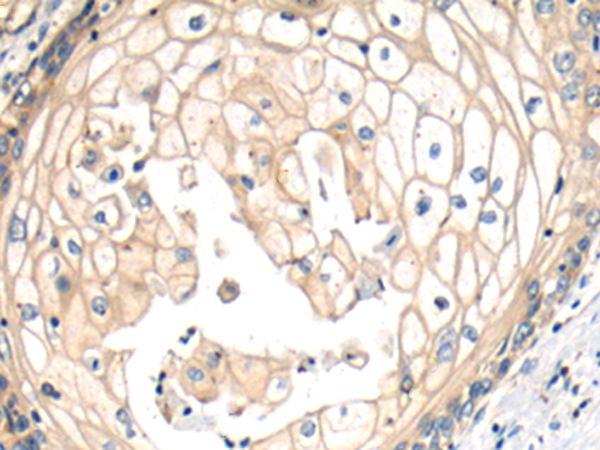

分类: 科研抗体货号: P11007别名: LSFC, GP130, LRP130, CLONE-23970应用: IHC反应种属: Human, Mouse, Rat